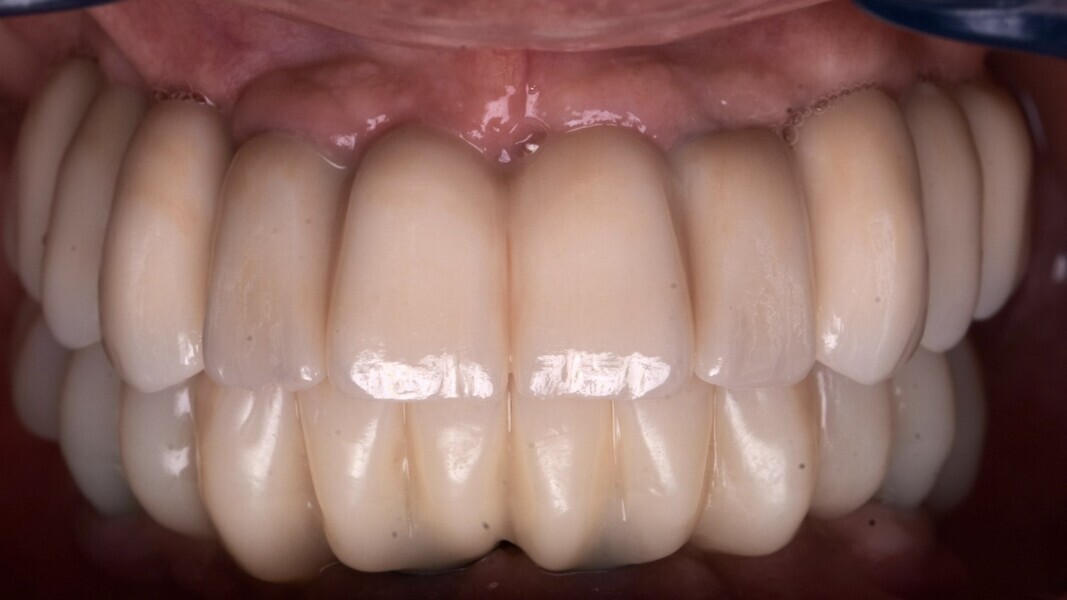

Les deux bridges provisoires sont vissés par l’intermédiaire de vario-bases à la mandibule et au maxillaire (Fig. 16). Nous réhabilitons le patient grâce à la réalisation d’un bridge full zircone à connexion directe sur multi-unit au maxillaire.

À la mandibule un bridge PMMA sur vario-base est vissé. Nous n’optons pas pour la réalisation de deux bridges full zircone, pour des questions de dureté de matériaux et de confort pour le patient. Nous combinons l’esthétique d’un bridge full zircone au maxillaire et la souplesse du PMMA à la mandibule (Fig. 17). La photo avant-après du patient, illustrant son état au premier jour et à la fin de son traitement, est présentée sur la figure 18.